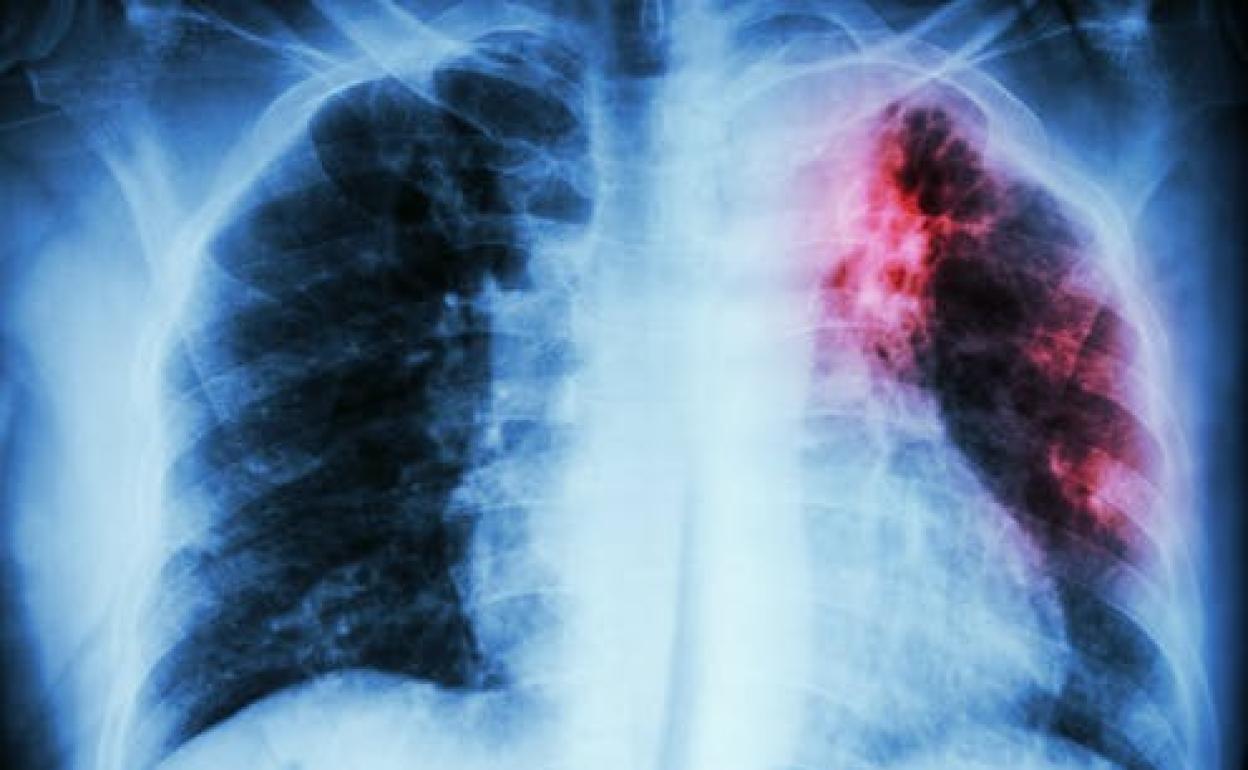

Tuberculosis y covid-19: ¿el nuevo dúo maldito?

La relación entre las enfermedades infecciosas más mortales del mundo despierta muchos interrogantes. ¿Qué sabemos de la coinfección entre ambas?

Tuberculosis y covid-19 son enfermedades infecciosas de transmisión aérea. Afectan mayoritariamente al sistema respiratorio y manifiestan una tríada clásica de síntomas: tos, fiebre y disnea. Esto dificulta inicialmente el diagnóstico diferencial, especialmente en países con alta incidencia de tuberculosis.